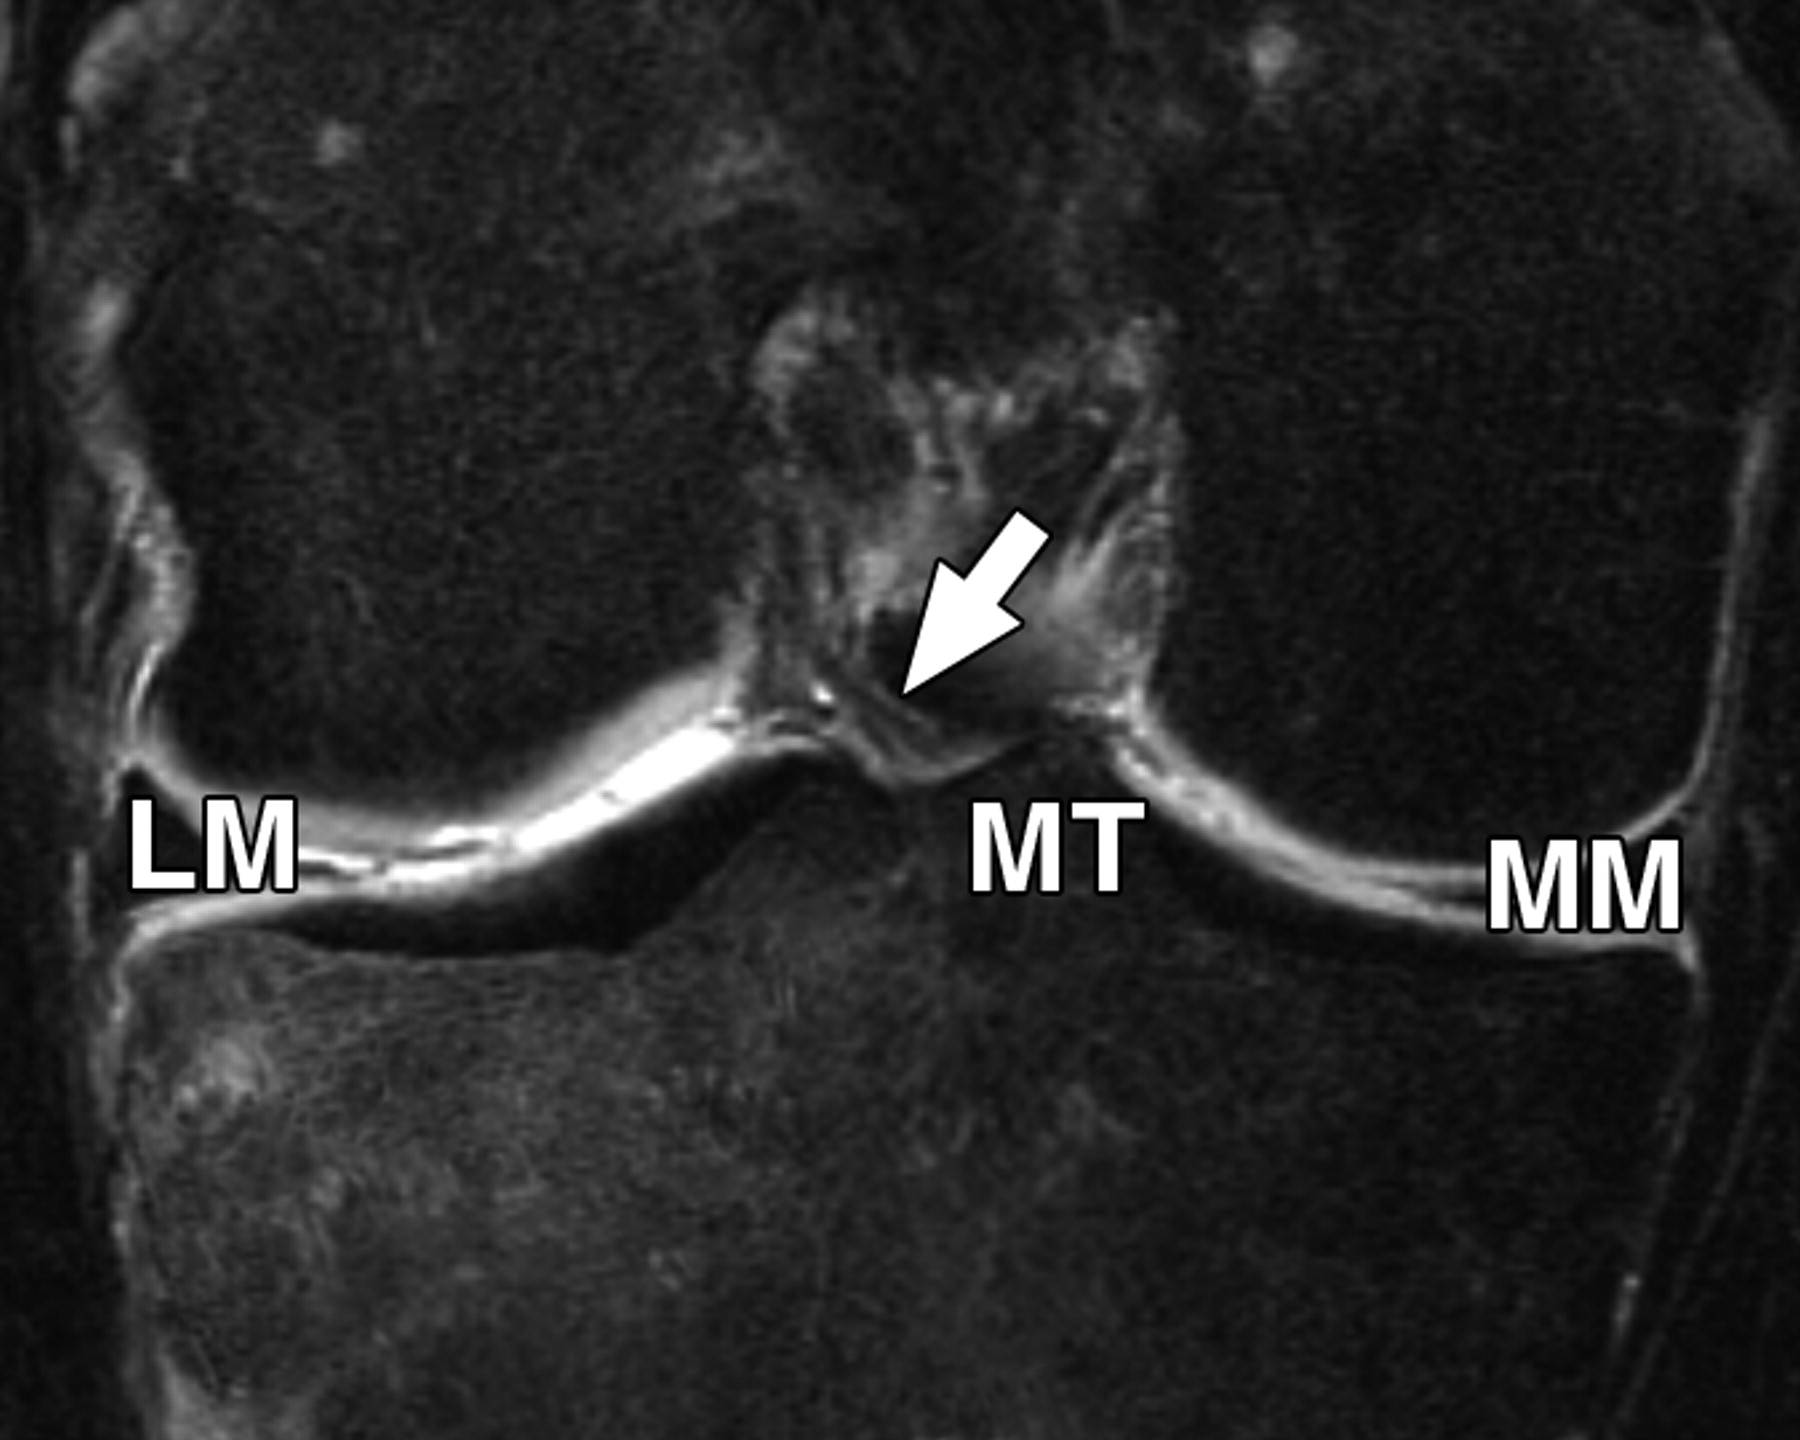

图5 B-59岁男性。中等加权、脂肪饱和、快速自旋回波(TR/TE有效值,3,700/29)3-T MR图像显示半月板后根和交叉韧带的解剖关系。

冠状面图像依次位于A的腹侧,显示外侧半月板后根(LM)(白色箭头)和内侧半月板后根(MM)(黑色箭头,B)的插入,覆盖后髁间区域的一个以上切片厚度。MT =胫骨内侧结节。